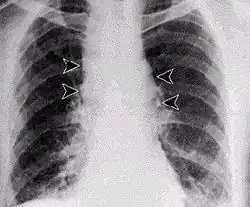

- Infecção pulmonar

A infecção pulmonar por carbúnculo provoca, nos primeiros dias, sintomas semelhantes aos da gripe, seguidos de problemas respiratórios graves, por vezes fatais. Se não for tratada, a infecção por inalação é a mais letal, com uma taxa de mortalidade de aproximadamente 90% a 100%. A infecção pulmonar também é conhecida por Doença de Woolsorter.